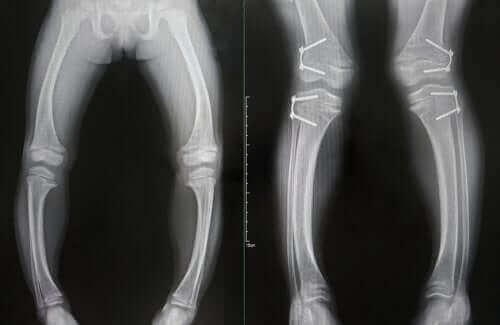

Rozpoznanie tej choroby opiera się na rozpoznaniu zmienionych wyników analitycznych i radiograficznych oraz obecności typowych objawów klinicznych.

Badania krwi dziecka mogą wykryć niski poziom fosforu i wapnia, a także enzymu fosfatazy alkalicznej lub witaminy D.

Leczenie polega na doustnym podawaniu kalcyferolu. Jednak nie jest to skuteczne w niektórych przypadkach zaawansowanej krzywicy lub w przypadku problemów z nerkami.